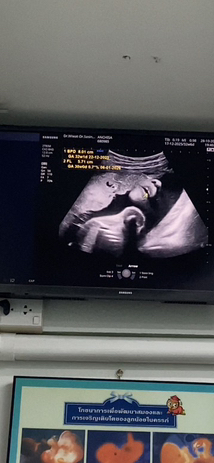

แบบนี้ปากแหว่งมั้ยคะ

แบบนี้คือปากแหว่งมั้ยคะแม่ๆ รอบที่แล้วซาวด์ตอน28w หมอบอกไม่แหว่ง อันนี้ตอน32+6w แม่เห็นดำๆตรงปากเลยกังวล แต่หมอไม่ได้บอกอะไร🥺

บางทีอาจจะเกิดจากมุมที่ซาวด์ได้ค่ะแม่ ตอนตรวจละเอียดได้เจอความผิดปกติมั้ยคะ

ตอนซาวด์28w หมอบอกปากไม่แหว่งค่ะแม่ รูปนี้คือซาวด์ตอน32+6หมอไม่ได้แจ้งอะไร แม่พึ่งมาสังเกตุรูปตอนกลับมาบ้านเลยสงสัย🥹